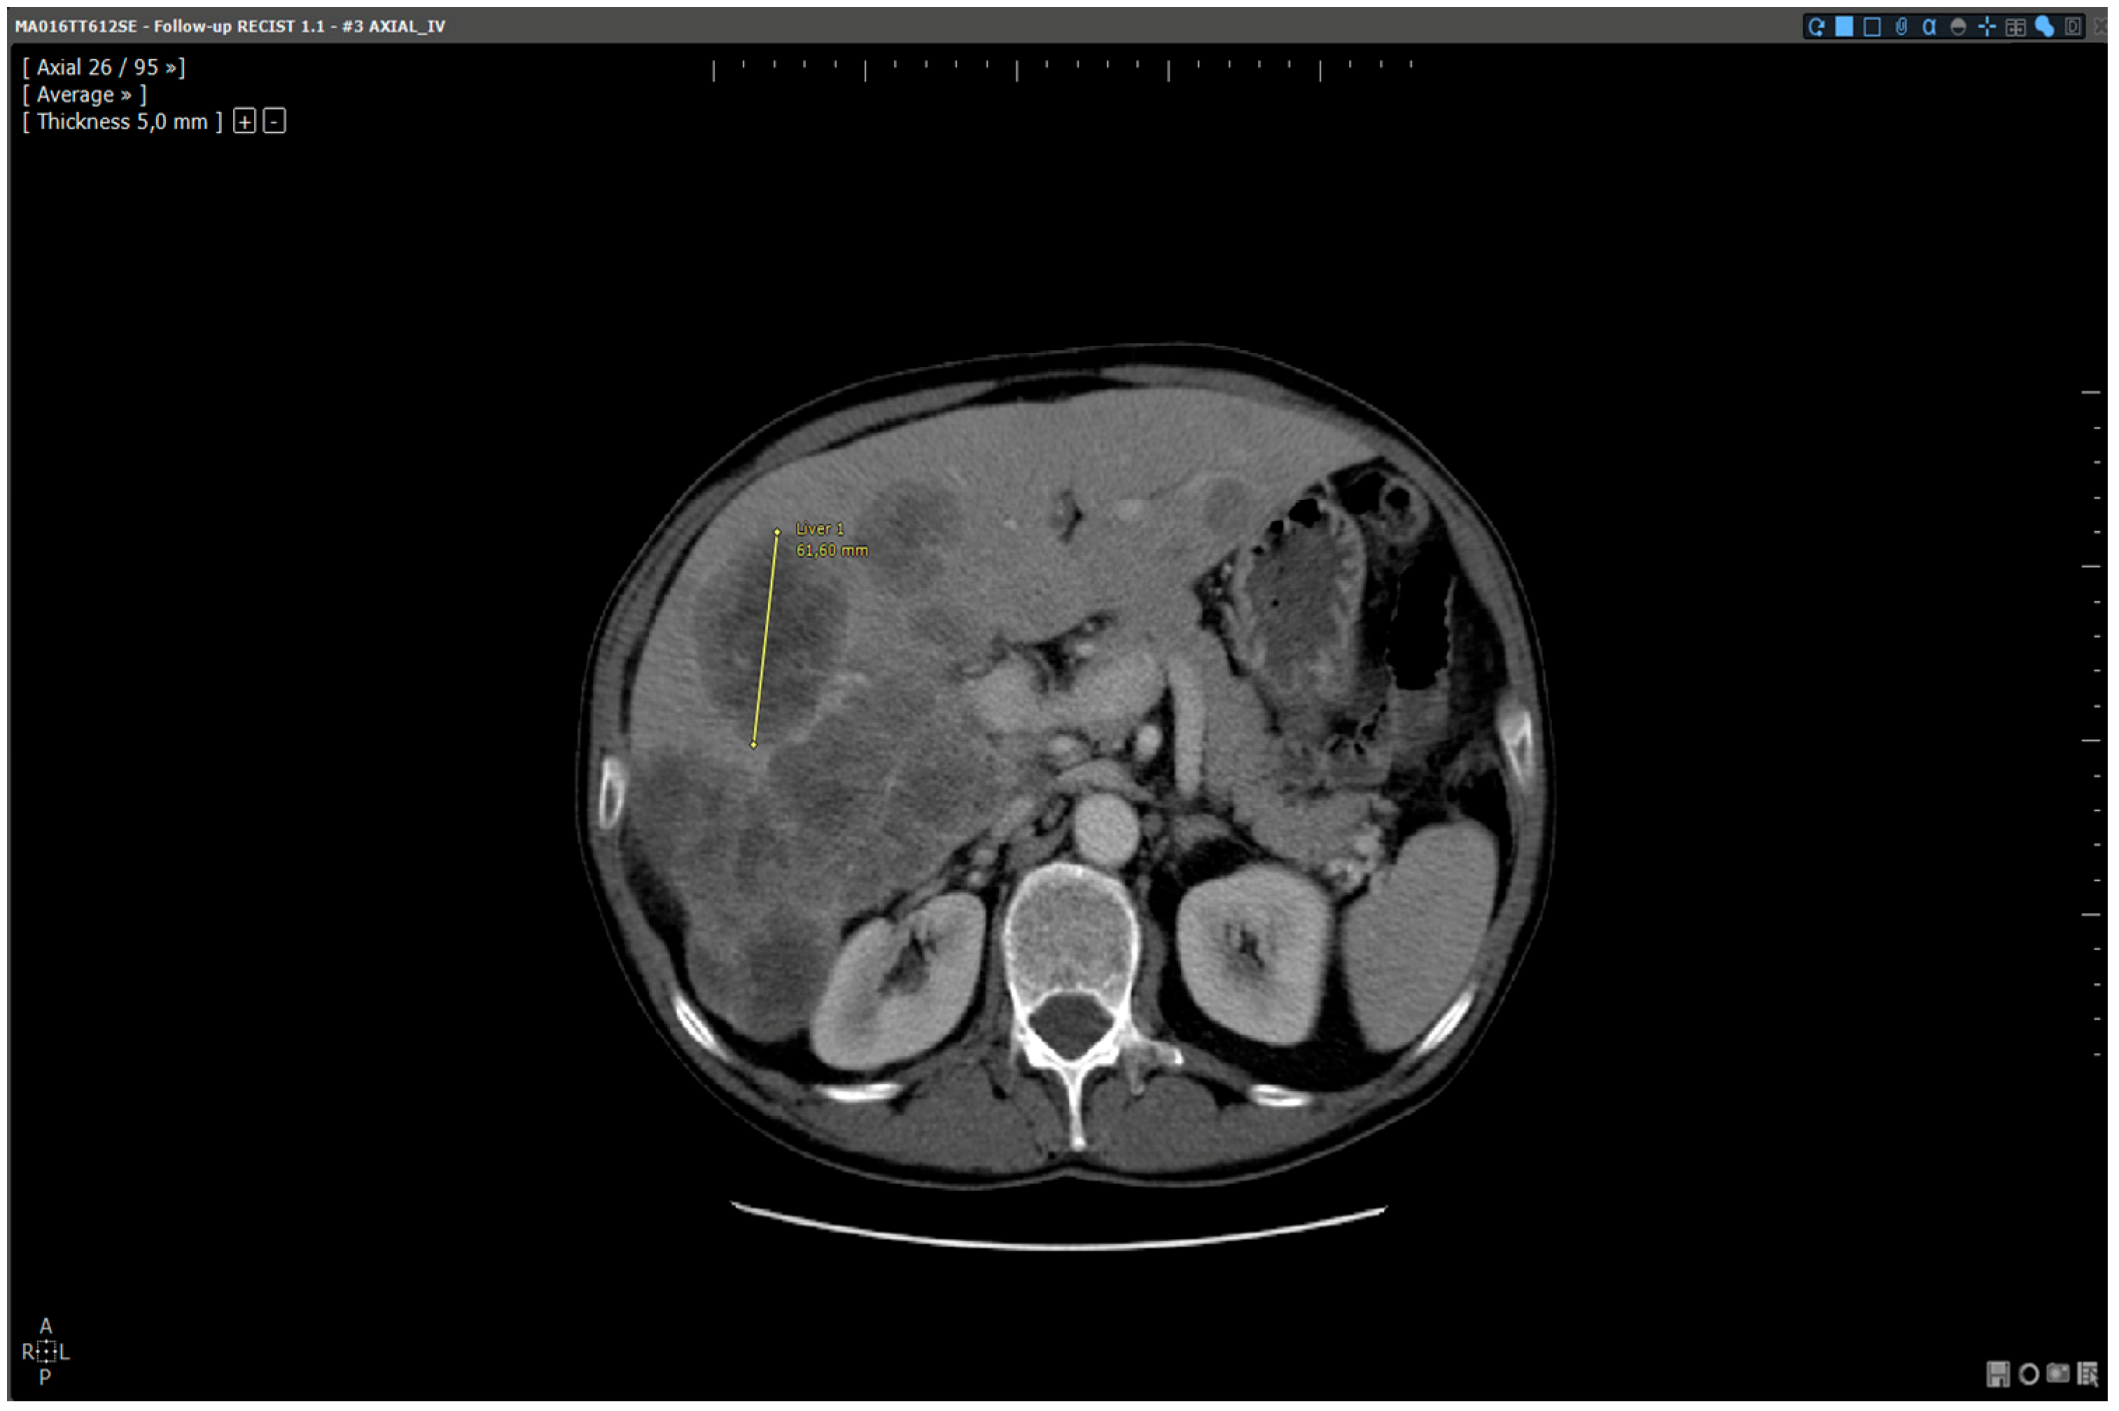

- Reading with dedicated software: Determination of RECIST response with the dedicated application for oncologic follow ups, Myrian® XL-Onco, with specific functionalities:

- Automated calculation of elements required for RECIST response determination (sum of diameters, percentage of tumour evolution, RECIST response (CR, PD, PR, and SD)),

- 3D target matching technology to facilitate lesion localisation in the follow up study.

| Step 2 | Baseline study opening | Manual | Automated |

| Step 3 | Target localisation on baseline study | Manual | Automated |

| Step 4 | Target localisation on follow up study | Manual | Automated |